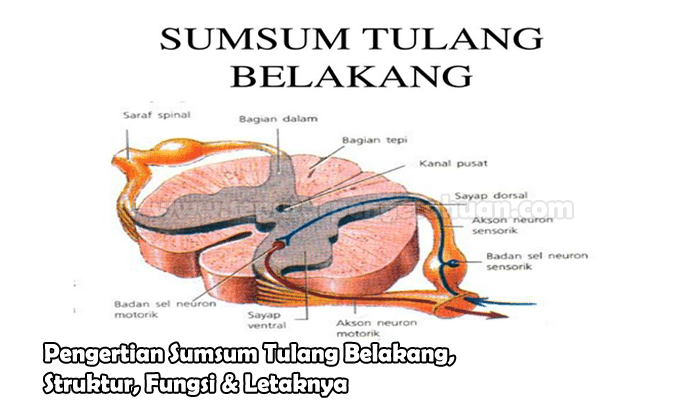

Sumsum Tulang Belakang Pengertian Letak Fungsi Struktur Dan Bagian Struktur Sumsum Tulang Belakang Medula Spinalis Manusia Lengkap

Sumsum Tulang Belakang Pengertian Letak Fungsi Struktur Dan Bagian Struktur Sumsum Tulang Belakang Medula Spinalis Manusia Lengkap

Pengertian Sumsum Tulang Belakang Fungsi Susunan Bagian

Pengertian Sumsum Tulang Belakang Fungsi Susunan Bagian

Sumsum Tulang Belakang Pengertian Struktur Fungsi Letaknya

Sumsum Tulang Belakang Pengertian Struktur Fungsi Letaknya

Sumsum Tulang Belakang Pengertian Fungsi Dan Strukturnya

Sumsum Tulang Belakang Pengertian Fungsi Dan Strukturnya

Struktur Dan Fungsi Sumsum Tulang Belakang Medula Spinalis Weschool Id

Struktur Dan Fungsi Sumsum Tulang Belakang Medula Spinalis Weschool Id

Pengertian Sumsum Tulang Belakang Bagian Susunan Fungsi

Pengertian Sumsum Tulang Belakang Bagian Susunan Fungsi